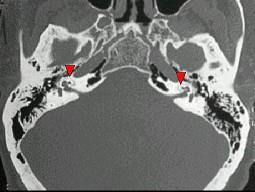

男,43岁,进行性双侧耳鸣、听力下降5年,双侧混合聋,CT所见如图,最可能的诊断 ( )

• A.耳硬化症

• B.膜迷路畸形

• C.嗜酸性肉芽肿

• D.骨化性迷路炎

• E.鼓室硬化症

答案: A